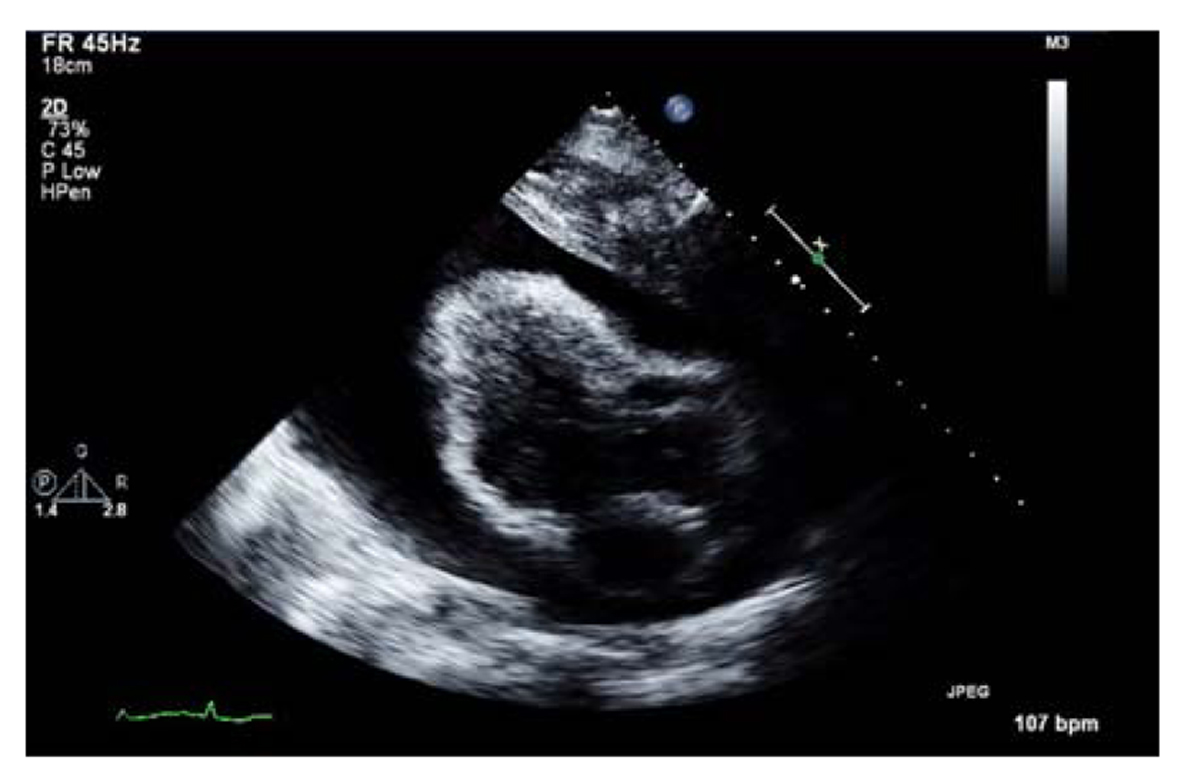

Transthoracic echocardiogram results confirmed a massive pericardial effusion measuring 5.5 - 6 cm (in largest diameter from apex) and a swinging heart (Fig. 4). These findings were compatible with a cardiac tamponade secondary to massive pericardial effusion.

![]() Click for large image | Figure 4. Transthoracic echocardiogram showing massive pericardial effusion. |